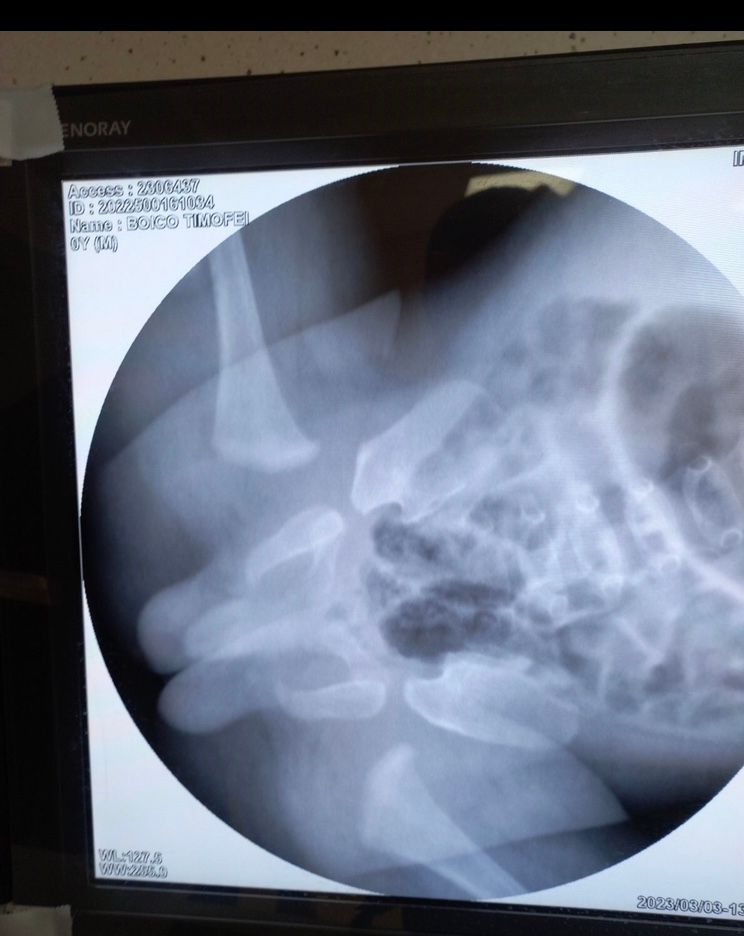

добрый вечер. у моего малыша дисплазия тбс с подвывихом. в марте вправили вывих и поставили гипс . хотелось бы узнать ваше мнение есть ли положительная динамика спустя два месяца в гипсе? нам немного изменили гипс и оставили его еще на два месяца.

Я удивлена, что вы в Питере, а лечитесь по московской школе - гипсом, а не шиной кошля. Мы в шине 24/7, на следующей неделе уже пол года как. По снимку сложно сказать. Желаю вам скорейшего выздоровления!